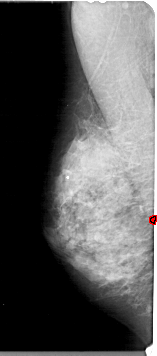

A_1926_1.RIGHT_MLO

RIGHT_MLO LINES 5491 PIXELS_PER_LINE 2266 BITS_PER_PIXEL 12 RESOLUTION 43.5 NON_OVERLAY

RIGHT_CC LINES 3886 PIXELS_PER_LINE 1756 BITS_PER_PIXEL 12 RESOLUTION 43.5 NON_OVERLAY